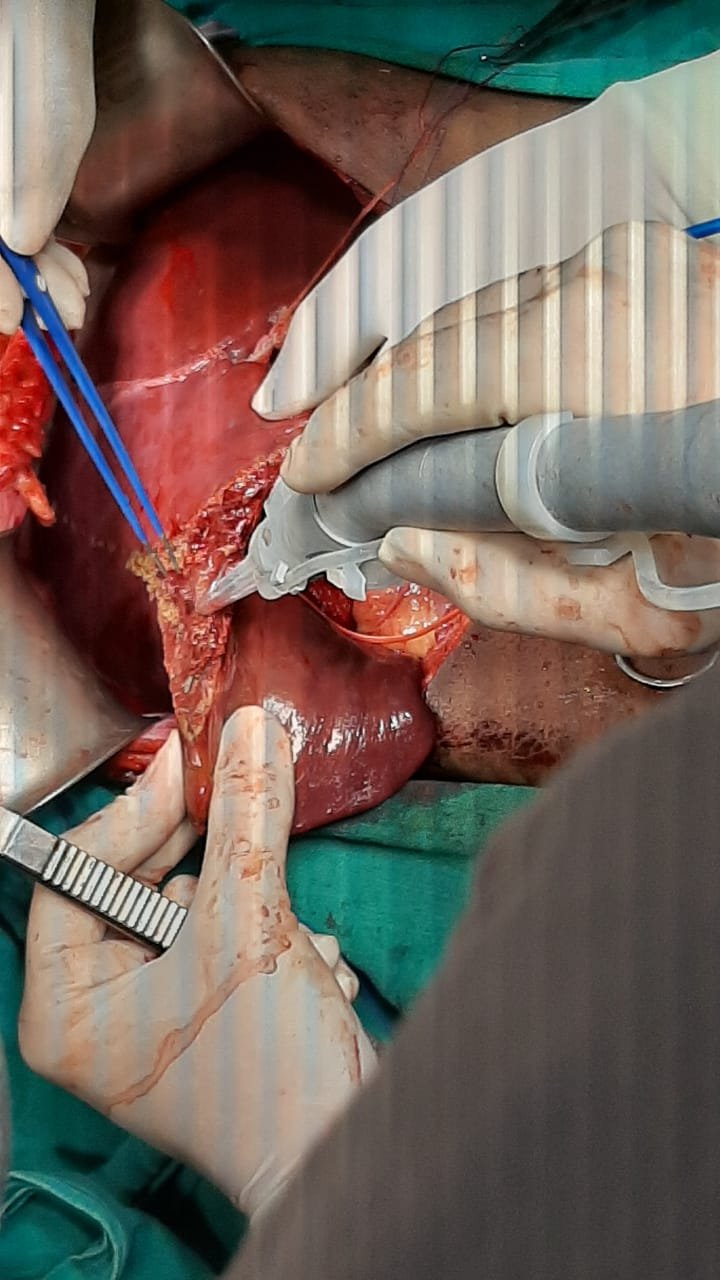

Liver Surgery performed was right hepatectomy for hepatoblastoma in seg 6,7 and 8 of liver; in 11 year old girl in SMS Hospital, Jaipur